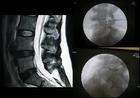

1.CT檢查:可清晰顯示椎體前、後緣的骨贅,硬脊膜囊、脊髓、神經根的受壓部位和程度,測得椎管前後徑和橫徑,還能了解椎間孔和橫突孔有無狹小,椎板有無肥厚等。2.拍X線片:是腰部疼痛病人的常規檢查。—般須攝正位、側位和左右斜位片,必要時加攝頸部前屈和後伸時的側位片。正位片可能見到椎間隙狹窄、鉤椎關節骨質增生,椎弓根增粗。側位片可發現頸椎生理前突消失,椎體前後緣形成骨唇,椎間隙狹窄和椎管狹窄。斜位片可判定椎間孔的情況。

3.磁共振:可清晰顯示間盤組織後突,壓迫硬脊膜囊和脊髓的情況,以及有無靜脈回流受阻、受壓,局部脊髓內有無囊性病變等情況。